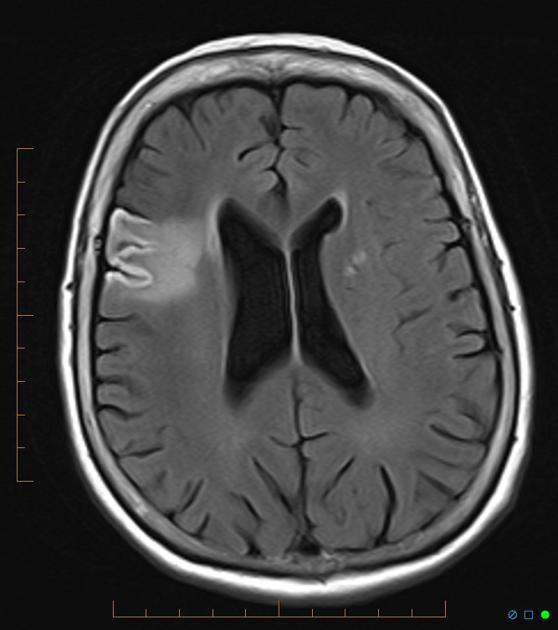

Cortical pseudolaminar necrosis

Cortical pseudolaminar necrosis, also known as cortical laminar necrosis and simply laminar necrosis, is the (uncontrolled) death of cells in the (cerebral) cortex of the brain in a band-like pattern with a relative preservation of cells immediately adjacent to the meninges.

It is seen in the context of cerebral hypoxic-ischemic insults, i.e. strokes.

Hyperintense on both T1 and T2!!!